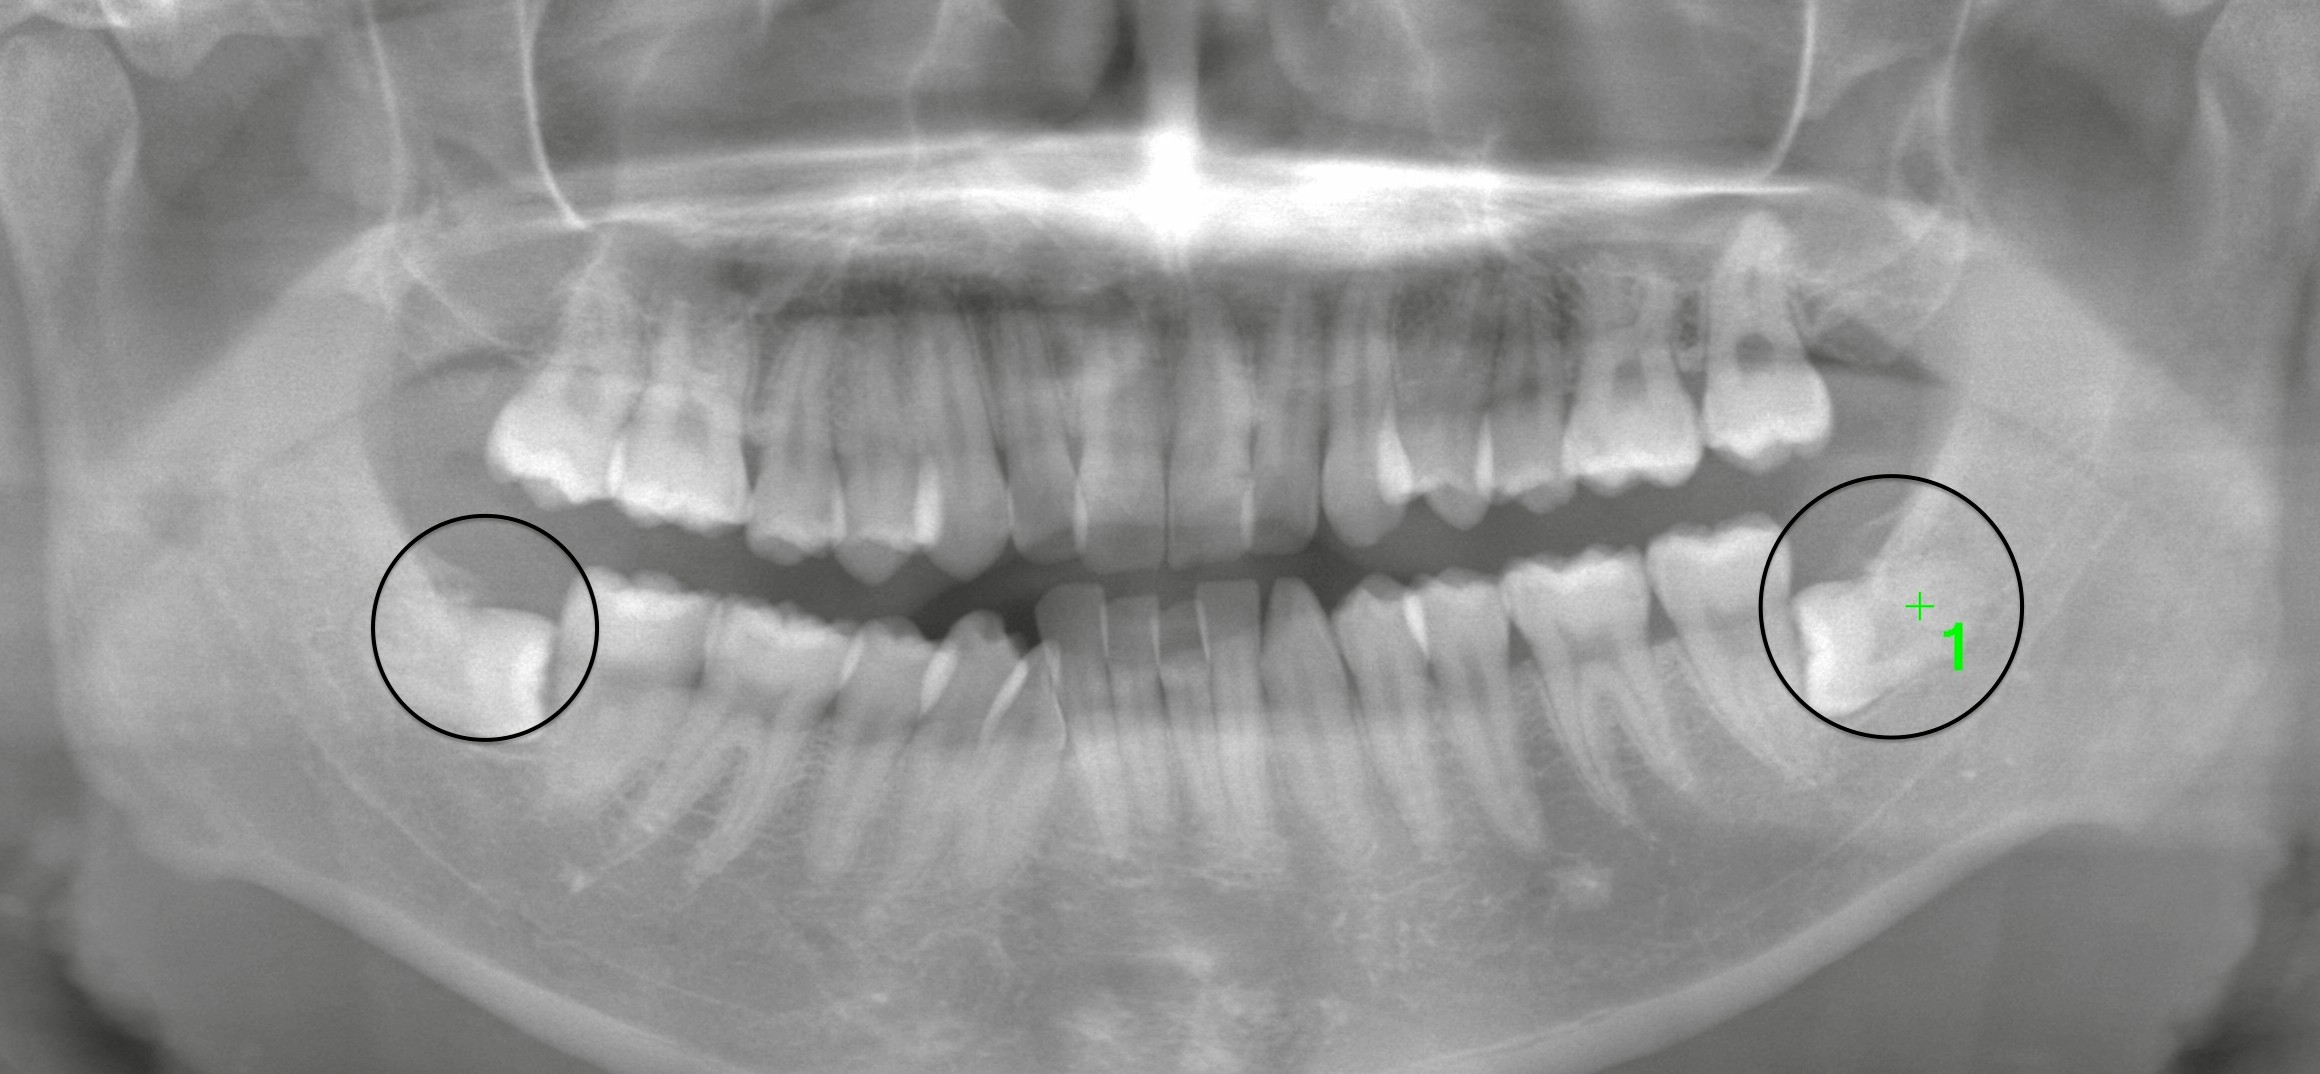

矯正前の親知らず抜歯-左右完全埋伏のケースについて

荻窪プラム矯正歯科様よりご紹介いただき、矯正治療前の左右の親知らず抜歯を希望されて来院されました。

診査の結果、左右とも完全埋伏の状態でした。

特に今回のような水平埋伏歯では、放置すると歯列全体に悪影響を及ぼすため、抜歯が推奨されます。

切開・分割を伴う水平埋伏抜歯でしたが、手術時間は数分で終了しました。